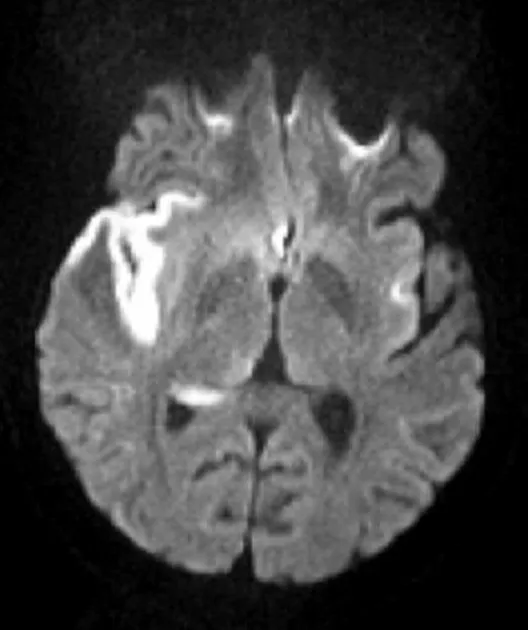

⭐ In HSV-1 encephalitis, look for personality changes (due to frontal/temporal lobe involvement) like hypomania or bizarre behavior. Treatment with acyclovir should not be delayed pending diagnostic confirmation.

- HSV-1: Most common cause of fatal sporadic encephalitis; temporal lobe necrosis.

Diagnosis: CSF analysis (lymphocytic pleocytosis, ↑ protein), PCR for viral DNA, and brain MRI.